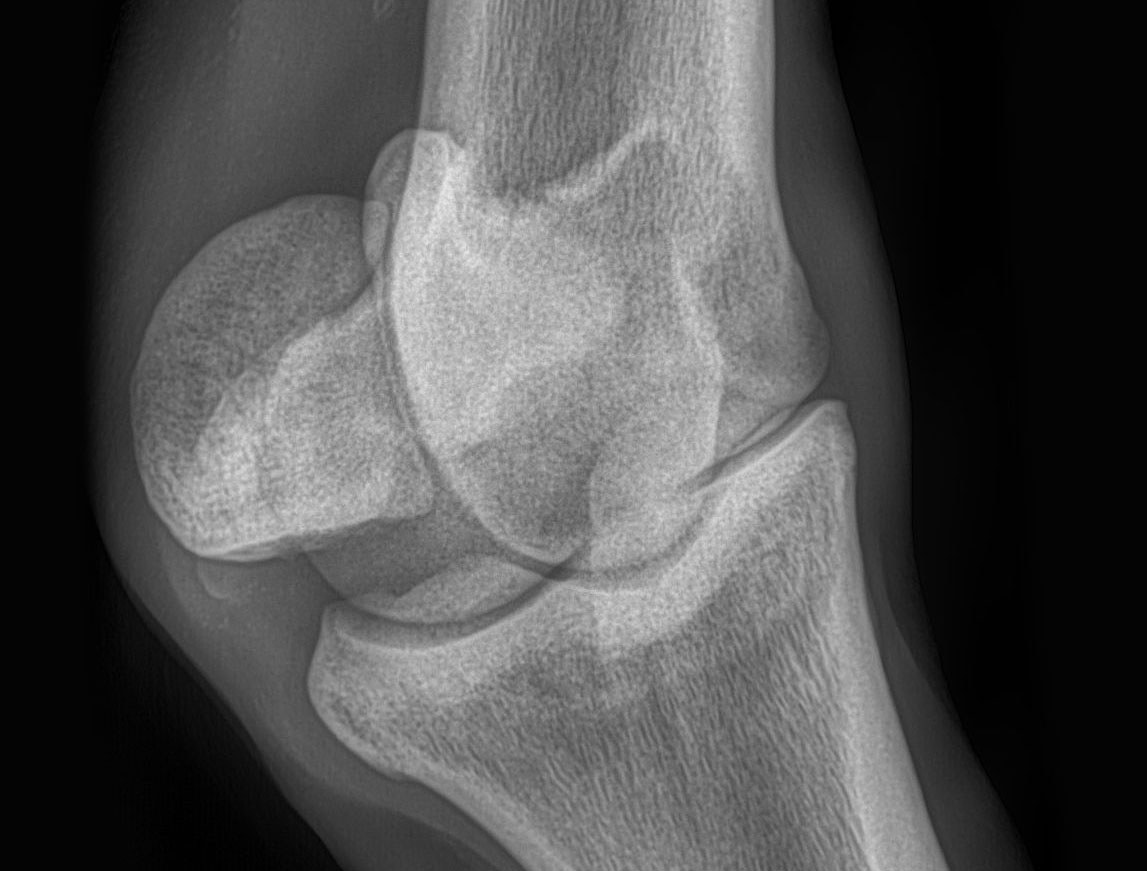

Jahre nach der Übergabe ein erheblicher Röntgenbefund, eine Lahmheit und die Frage : ist das Pferd auf Grund eines unstreitig zum Übergangszeitpunkt bereits bestandenen erheblichen Röntgenbefundes hinten rechts (Apikalfraktur eines Gleichbeins) i.V.m. einer wenig nach der Übergabe tierärztlich bescheinigten „akuten Lahmheit“ als Reitpferd unbrauchbar ?

Nein – die Lahmheitsursache war jedenfalls zum Besichtigungszeitpunkt nicht im Bereich des bereits zum Übergabezeitpunkt vorhandenen Röntgenbefundes (Gleichbeinfraktur) lokalisiert, sondern deutlich oberhalb des Fesselgelenkes.

1. Ein Röntgenbefund ist als solcher grundsätzlich nicht geeignet, eine Lahmheitsursache abzuklären.